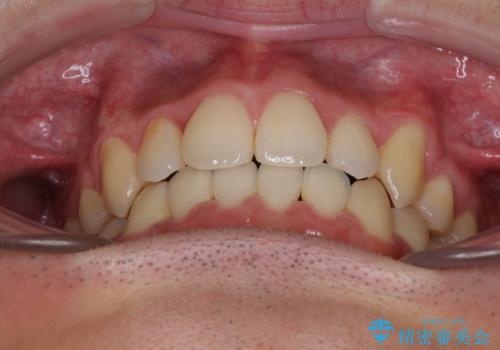

- 上下の八重歯や乱杭歯を気にして来院され患者様です。

スペースを確保するため、上下左右の小臼歯を抜歯し、ワイヤー装置に矯正することとしました。

奥歯の咬み合わせの左右差が大きかったため、変則的な抜歯矯正を行いました。

治療期間はやや長期化しましたが、満足のいく歯並びとなりました。